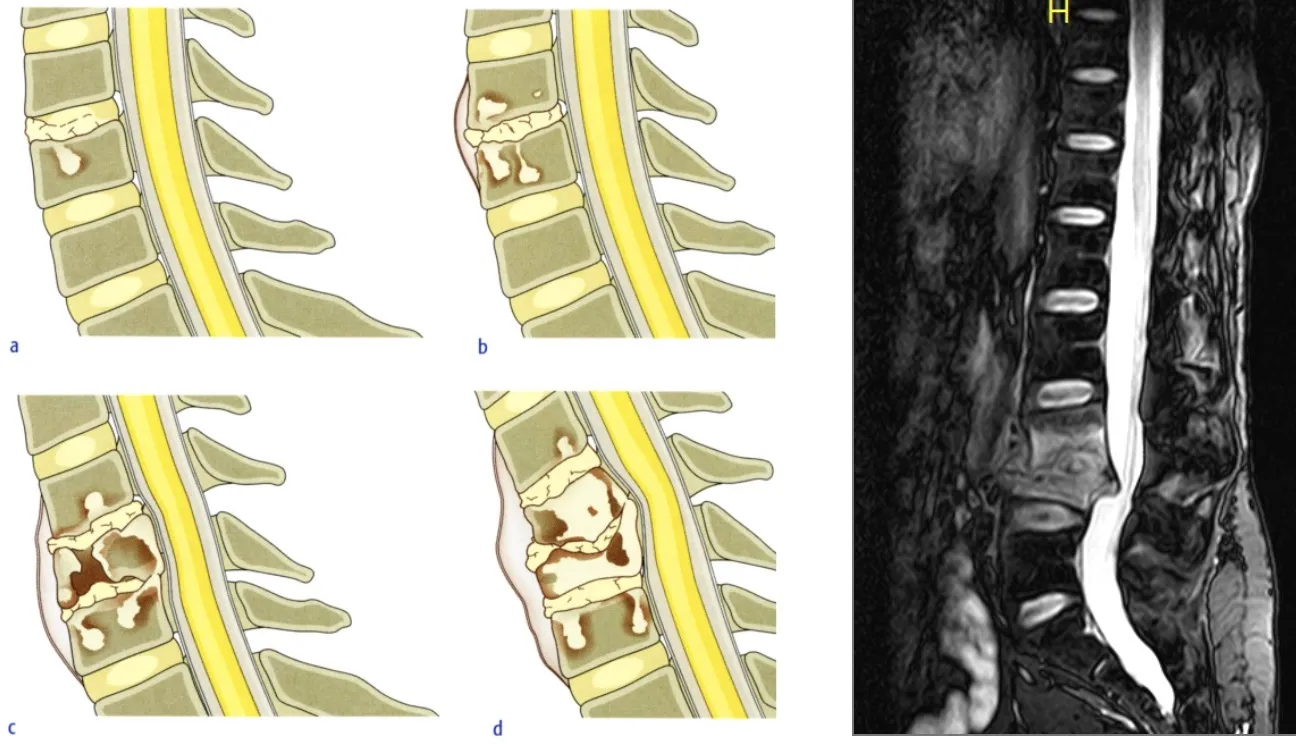

La clasificación de la espondilodiscitis por resonancia magnética distingue diferentes estadios según los hallazgos radiológicos:

| Estadio | Hallazgos |

|---|---|

| Estadio I | Hematoma y radiolucidez localizada en los platillos de la vértebra |

| Estadio II | Edema vertebral y/o sospecha de acumulación de líquido dentro del cuerpo vertebral con mala demarcación de la lesión |

| Estadio III | Intensidad de señal irregularmente aumentada en la resonancia con confinamiento dentro del ligamento longitudinal posterior |

| Estadio IV | Acumulación evidente de líquido en el disco asociado a destrucción de los platillos y extensión a lesiones epidurales |

| Estadio V | Desaparición del disco con colapso vertebral y afectación del cuerpo vertebral y arco posterior así como de los ligamentos y músculos paravertebrales |